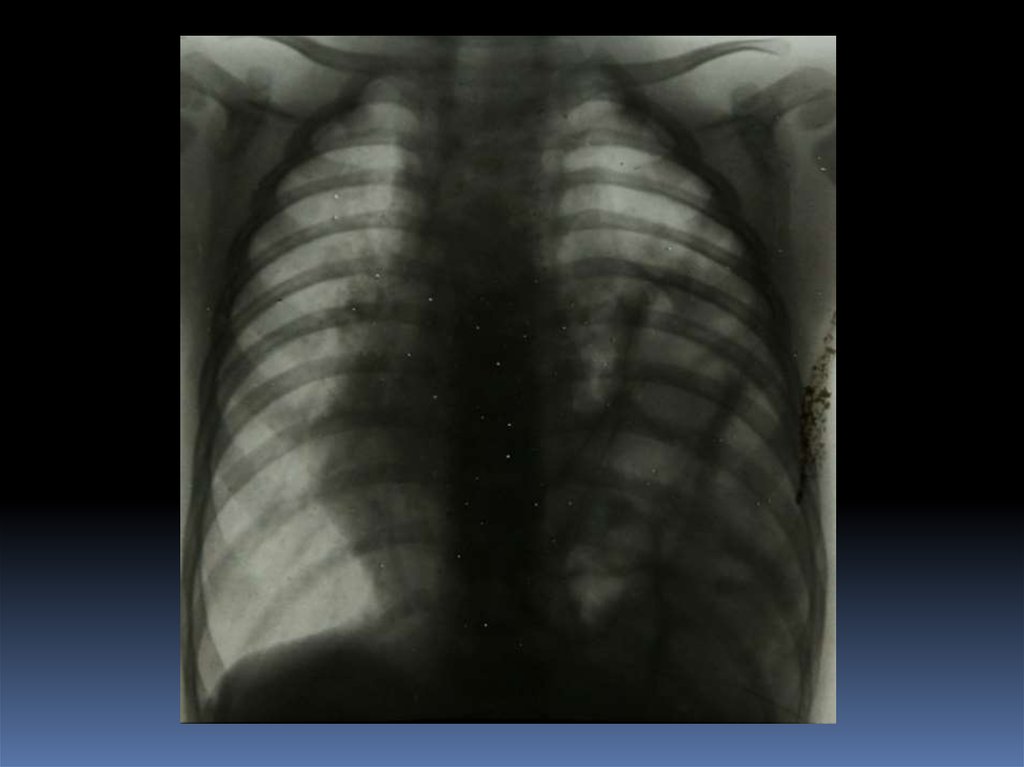

5. Проведение рентгеноскопического исследования раненого.

6. Проведение рентгенографического исследования раненого.

7. Виды травматического повреждения грудной клетки:

пневмоторакс;

гемоторакс;

гемопневмоторакс;

внутрилегочные гематомы;

дисковидные ателектазы;

посттравматические пневмонии.